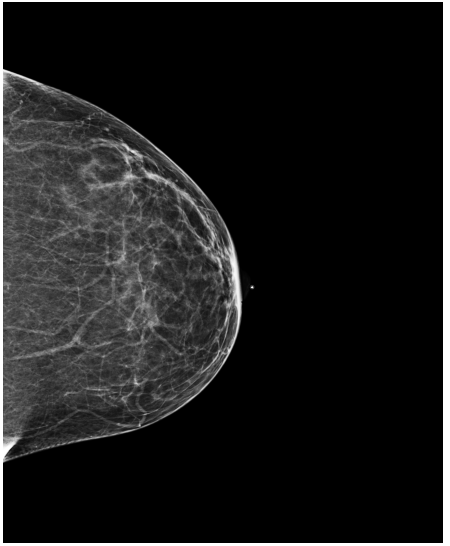

4.3 Pre-processing

The EMBED and CSAW-CC datasets originally consist of images in DICOM format, which are converted into 16-bit grayscale PNG images for consistency and compatibility. Following the pre-processing procedure outlined in (Yala et al.,, 2021), we enhanced image quality and removed background artifacts—such as textual annotations commonly present in mammography images—by applying a contour detection procedure. All contours in the image are detected, and only the largest contour, corresponding to the breast tissue, is retained. This contour is then used to create a mask that isolates the breast region from the background. The isolated breast image is resized to a size of 1664×20481664\times 2048 pixels while preserving the aspect ratio. Finally, the resized image is normalized and converted to a 16-bit format.